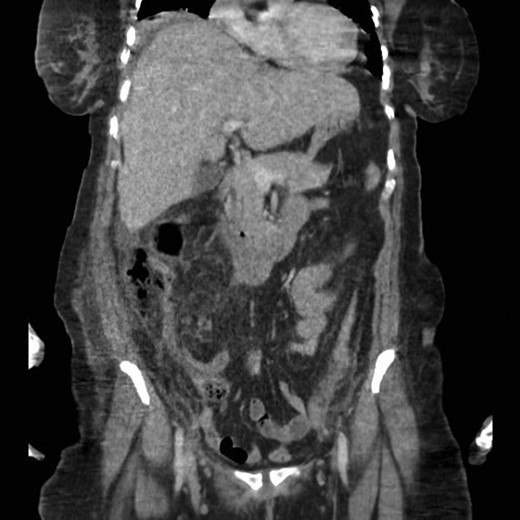

A second abdominal CT scan showed an ill-defined retroperitoneal collection, mainly on the right side. In fact, two pockets of collection in the right retroperitoneal area were observed: the first pocket was just under the abdominal muscles and peripherally, and the second pocket was just anterior to Gerota’s fascia of the right kidney.

An ultrasound-guided drainage procedure successfully drained 300 ml of pus.